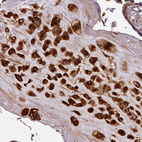

Immunohistochemical staining of human placenta shows strong nuclear and cytoplasmic positivity in decidual cells.